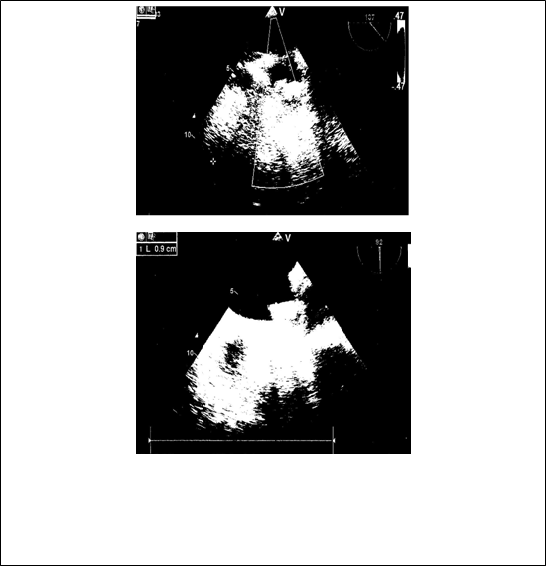

Материал и методы: с 2013 по 2015г. в Центральной клинической больнице №2 им Н.А. Семашко ОАО «РЖД», было имплантировано 15 окклюдеров «WATCHMAN» пациентам с персистирующей формой фибрилляции предсердий неревматической этиологии, поступившим для выполнения электроимпульсной терапии, электрофизиологического исследования и радиочастотной аблации, имплантации электрокардиостимулятора. Показаниями к эндоваскулярному вмешательству были угроза повторных тромбоэмболий, высокий риск кровотечений, наличие тяжелой сопутствующей соматической патологии, неэффективность консервативной антикоагулянтной терапии. Из исследования исключались пациенты со стенозом левого атриовентрикулярного отверстия, тромбами в ушке левого предсердия. На дооперационном этапе всем пациентам выполнялась стандартная трансторакальная эхокардиография и чреспищеводная эхокардиография, для оценки анатомии ушка левого предсердия, определения его размеров в четырех проекциях, а также взаимоотношение ушка левого предсердия и левой верхней легочной вены. Для оценки риска инсульта и тромбоэмболических событий использовалась шкала CHA2DS2 и ее новая модификация CHA2DS2-VASc. Перед выпиской из стационара всем оперированным больным проводилась контрольная чреспищеводная эхокардиография, которую повторяли в послеоперационном периоде через 1.5, 6 и 12 месяцев.

Результаты: средний возраст больных составил 52 года. Всем пациентам процедура имплантации окклюдера «WATCHMAN» проведена успешно. Вмешательства выполнялись без использования общего наркоза, под местной анестезией. Средняя продолжительность операции составила 42±11,3мин. На каждого пациента было использовано по одному устройству. Смены окклюдера в связи с неверным определением размера или другими причинами не было. У 5 пациентов (анатомическая форма ушка «chicken wing») под углами 90 — 135° интраоперационно выявлена протрузия нижнего края окклюдера до 1/3 длины. У пациентов с имплантированным в УЛП окклюдерами 33 и 27 размерами, по нижнему краю регистрировался резидуальный поток диаметром 5мм и 2 мм соответственно. Осложнений во время операции, так и в ближайшем послеоперационном периоде не зарегистрировано. Через 12 месяцев наблюдения изменений положения окклюдера и наличие тромбов на поверхности окклюдера и в УЛП ни у одного пациента не зарегистрировано. Не отмечено дислокации, эмболизации, изменения положения устройств. Диаметр резидуального потока по нижнему краю импланта 33 размера у одного пациента через 6 месяцев уменьшился с 5 мм до 2 мм, у другого остался прежним – 2 мм. Ни у одного пациента не были зафиксированы эпизоды нарушения мозгового кровообращения, а также другие тромбоэмболические события.